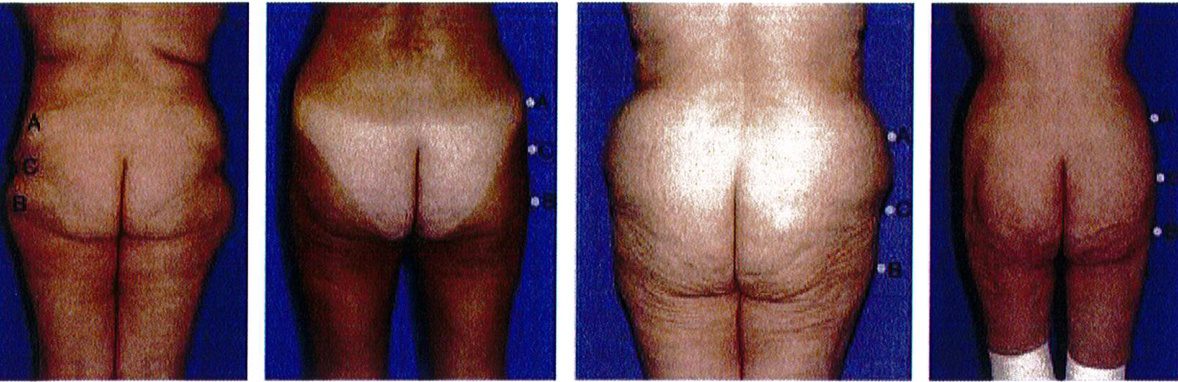

Khung chữ A gặp ở khoảng 30% bệnh nhân. Khi nối các điểm A và B, tạo ra hình dạng gần như chữ A (Hình 11). Hình dạng này đặc biệt vì chúng tích nhiều mỡ ở hơn ở vùng đùi ngoài phía trên (điểm B) và ít chất béo hơn ở vùng hông bên (điểm A). Lý tưởng nhất là điểm A nhô ra nhiều hơn một chút. Lúc này, khi rút chất béo ở điểm B đi, mông bắt đầu có dạng vuông. Điểm C có thể bị lõm đi nhiều, song ở dạng này hầu hết các trường hợp chỉ lõm mức nhẹ hoặc trung bình.

Khung chữ A gặp ở khoảng 30% bệnh nhân. Khi nối các điểm A và B, tạo ra hình dạng gần như chữ A (Hình 11). Hình dạng này đặc biệt vì chúng tích nhiều mỡ ở hơn ở vùng đùi ngoài phía trên (điểm B) và ít chất béo hơn ở vùng hông bên (điểm A). Lý tưởng nhất là điểm A nhô ra nhiều hơn một chút. Lúc này, khi rút chất béo ở điểm B đi, mông bắt đầu có dạng vuông. Điểm C có thể bị lõm đi nhiều, song ở dạng này hầu hết các trường hợp chỉ lõm mức nhẹ hoặc trung bình. Dạng khung này thường được cải thiện khi hút mỡ ở điểm B hoặc vùng đùi bên (Hình 12). Điểm C có thể cần ghép mô mỡ, tùy thuộc vào mức độ lõm. Nên tránh hút mỡ quá nhiều ở điểm B để ngăn chặn điểm lõm ở khu vực này, ngẫu nhiên hình thành ranh giới giữa vùng mông và mặt ngoài đùi.

Dạng khung này thường được cải thiện khi hút mỡ ở điểm B hoặc vùng đùi bên (Hình 12). Điểm C có thể cần ghép mô mỡ, tùy thuộc vào mức độ lõm. Nên tránh hút mỡ quá nhiều ở điểm B để ngăn chặn điểm lõm ở khu vực này, ngẫu nhiên hình thành ranh giới giữa vùng mông và mặt ngoài đùi.

Hình. 11. Hình minh họa khung dạng chữ A với mức độ lõm nhẹ, trung bình và nhiều ở điểm C. Điểm A nên là điểm lồi ra nhiều nhất của vùng mông ở dạng này, nên sẽ thực hiện hút mỡ ở điểm B để cân đối lai.

Hình. 12. Khung mông dạng chữ A, cao trước (bên trái) và sau (bên phải) nâng mông thẩm mỹ.